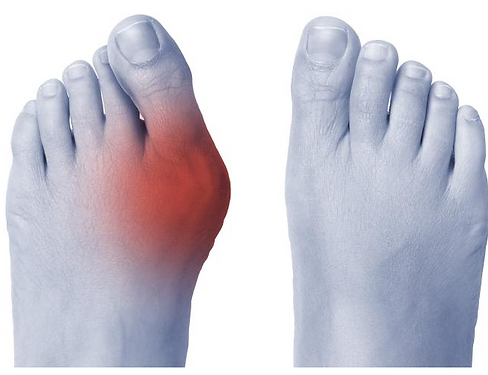

Hallux Valgus

L’hallux valgus, communément appelé « oignon », est une déformation du gros orteil (hallux) vers le dehors (valgus). Cette condition se caractérise par la présence d’une bosse à la base du gros orteil, douloureuse et inesthétique, qui correspond à une excroissance osseuse (exostose). En l’absence de traitement, cette bosse peut s’agrandir avec le temps et provoquer une rougeur ou une inflammation sur le côté du pied, connue sous le nom de bursite.

Les manifestations cliniques de l’hallux valgus sont généralement aisément identifiables. Elles se traduisent par une déviation progressive du gros orteil vers l’extérieur, pouvant, dans les formes évoluées, entraîner un chevauchement du second orteil.

Cette déviation s’accompagne d’une désaxation de l’articulation métatarso-phalangienne du premier rayon, à l’origine de la formation d’une saillie osseuse caractéristique sur le bord interne de l’avant-pied, communément appelée « oignon ».

L’évolution de cette déformation s’associe fréquemment à des phénomènes inflammatoires locaux liés aux conflits répétés avec le chaussage, se manifestant par des rougeurs, des douleurs, voire des épisodes d’irritation ou d’infection au niveau de la zone de frottement.